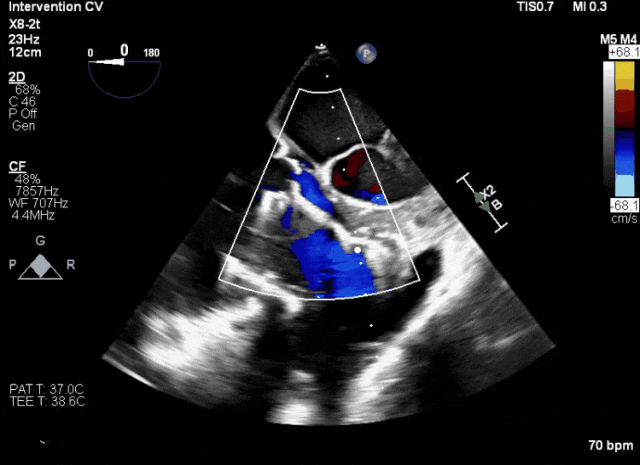

術中TEE成像困難,偽影干擾